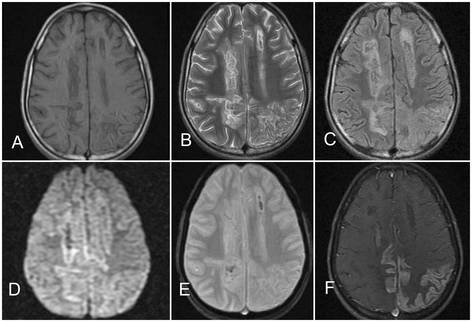

15岁男孩,表现为发热,头痛和感觉异常12天。入院时有发热(38.3℃),皮肤无瘀点瘀斑,无局灶性神经功能缺失症状,但包括脑膜刺激征在内的神经系统查体均无殊。实验室检查提示血红蛋白11g/dl,白细胞计数3300/mm3,血小板计数22000/mm3,但第二天跌至8000/mm3,天门冬氨酸氨基转移酶155U/L,丙氨酸氨基转移酶140U/L,碱性磷酸酶56U/L。其他生化指标,肾功能,血糖,电解质,动脉血气分析等正常。外周血涂片未见疟原虫。脑脊液常规和生化检查正常。脑电图可见全面性慢波。头颅MRI可见双侧顶枕叶和左侧额叶异常信号(左侧半球病灶较右侧半球更明显)。双侧基底节区可见轻度T2高信号。注射对比剂后可见脑回样强化,提示皮质层状坏死(图1)。

(图:A:T1WI;B:T2WI;C:FLAIR;可见双侧顶叶和枕叶曲线样高信号皮层病灶;D:DWI上可见轻度脑回弥散受限;E:梯度回波序列可见病灶伴出血;F:增强T1可见脑回样强化病灶)